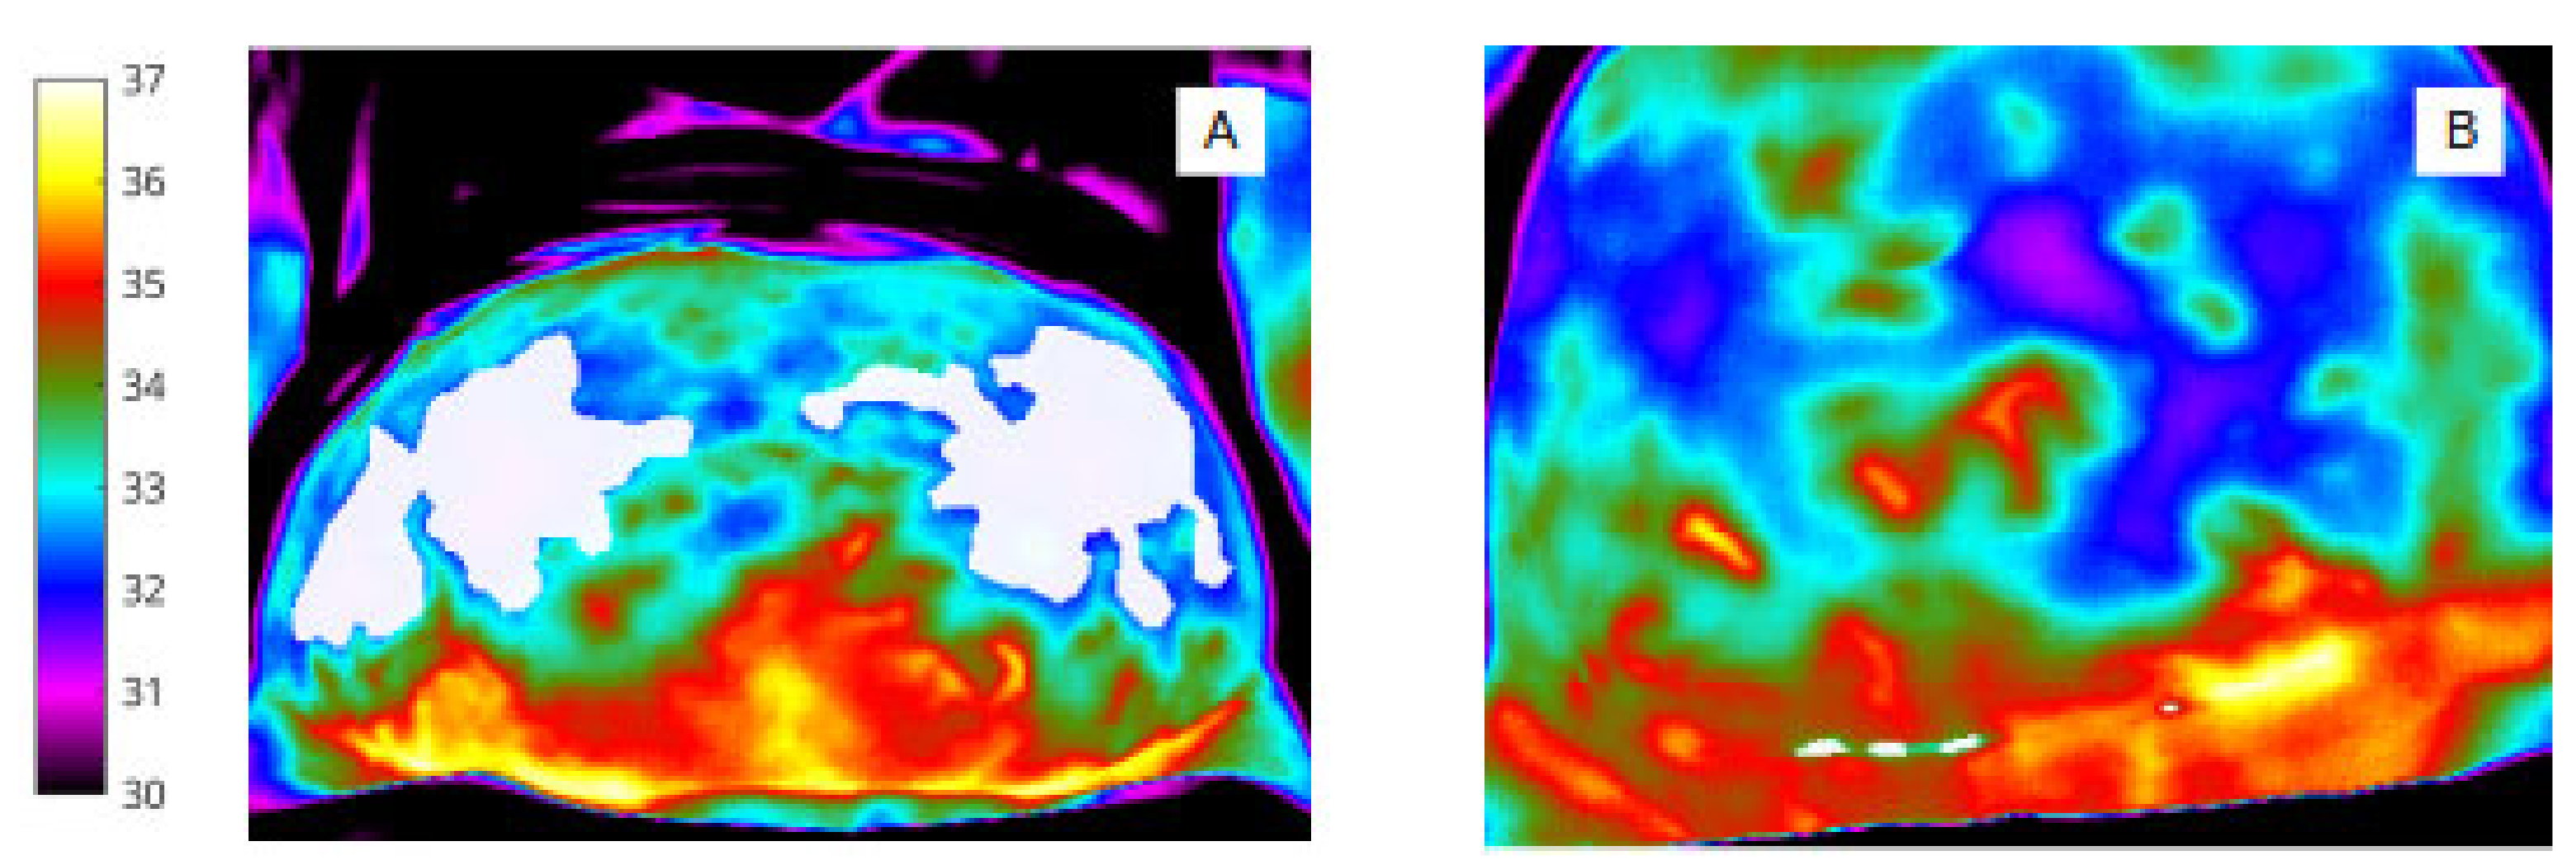

To identify pixel clusters of low temperature, shown qualitatively by the (rainbow) colour palette on the thermal image (Figure 4), automated minima regions were selected using MATLAB (by choosing continuous regions within the ROIs that are 0.5 degrees or more cooler than the surrounding areas) to produce pixel masks within the image bounding box (abdomen and wound).

Figure 4.

‘Object’ labels identify extent and site of abdominal skin ‘cold regions’ (A) and wound ‘cold spot’ clusters, (B) (shown in white for clarity in this image).